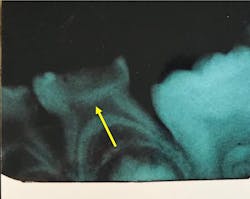

What I saw was astonishing! The abscesses stopped. The pain from active decay stopped. When we finally got into the hospital OR, it was clear that all lesions had become arrested, and that tertiary dentin was forming beneath arrested lesions (figure 2).